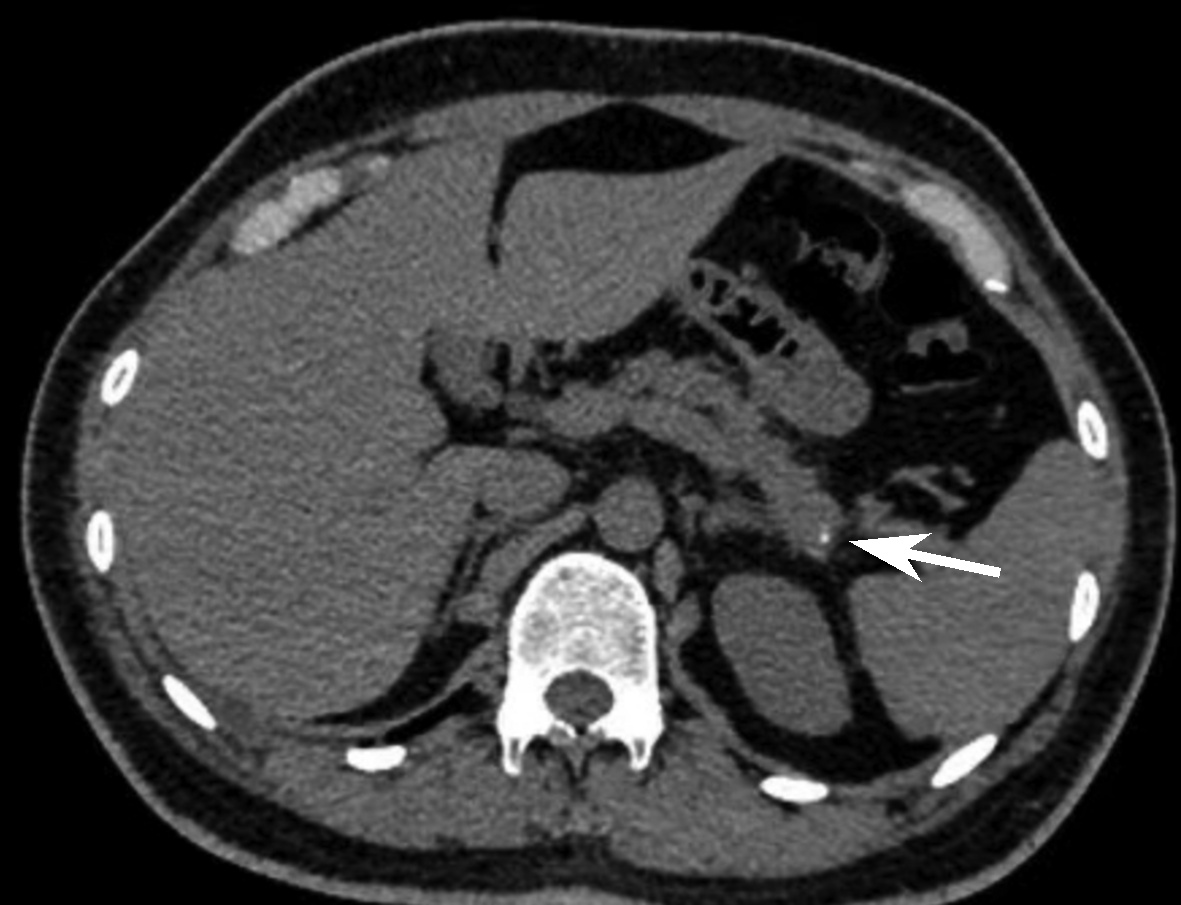

Selection of treatment regimens for pancreatic duct stones: A comparative analysis

Jinbin DONG, Weibing FANG, Yihai SHI

2022, 38(11): 2558-2564. DOI: 10.3969/j.issn.1001-5256.2022.11.023

Abstract(839) HTML (936) PDF (2050KB)(88)

Abstract:

Objective  To investigate the clinical efficacy of endoscopic retrograde cholangiopancreatography (ERCP), laparoscopy, and laparotomy in the treatment of pancreatic duct stones (PDS) by collecting related clinical data, to summarize the experience in selecting treatment regimens for PDS, and to further explore feasible treatment regimens that could maximize and optimize the benefits of PDS patients.  Methods  A retrospective analysis was performed for the clinical data of 131 PDS patients who were treated in Gongli Hospital Affiliated to Naval Medical University from June 2014 to December 2018, and according to the surgical procedure, they were divided into ERCP group with 69 patients, laparoscopy group with 32 patients, and laparotomy group with 30 patients. Related indices were monitored before and after treatment, and surgical outcome was compared between the laparoscopy group and the laparotomy group. The independent samples t-test was used for comparison of normally distributed continuous data between two groups; a one-way analysis of variance was used for comparison between multiple groups, and the least significant difference t-test or the SNK-q test was used for further comparison between two groups. The Mann-Whitney U test was used for comparison of continuous data with skewed distribution between two groups, and the Kruskal-Wallis H test was used for comparison between multiple groups. An repeated measures analysis of variance and the Friedman test were used for comparison of related indices before and after surgery, and the chi-square test was used for comparison of categorical data between groups.  Results  Among the 131 PDS patients, there were 40 patients with type Ⅰ PDS, 76 with type Ⅱ PDS, and 15 with type Ⅲ PDS. There was no significant difference in the distribution of main surgical methods between the laparoscopy group and the laparotomy group (χ2=1.93, P > 0.05). There were significant differences between the laparoscopy group and the laparotomy group in the dynamic changes of white blood cell count, C-reactive protein, procalcitonin, and Homeostasis Model Assessment of Insulin Resistance after surgery (F=24.68, χ2=227.66, F=45.37, F=106.71, all P < 0.05). Compared with the laparotomy group, the laparoscopy group had significantly shorter time of operation, significantly lower intraoperative blood loss, significantly shorter time to first flatus after surgery, a significantly lower frequency of use of pain-relieving drugs, shorter time to extraction of abdominal drainage tube, lower incidence rates of short-term postoperative complications, and a significantly shorter length of postoperative hospital stay (t=-4.80, t=-9.43, Z=-6.78, t=-11.59, Z=-6.77, χ2=9.24, t=-3.60, all P < 0.05). The incidence rate of short-term postoperative complications was 24.64% in the ERCP group, 28.13% in the laparoscopy group, and 66.67% in the laparotomy group, with a significant difference between groups (χ2=17.12, P < 0.05), and the ERCP group and the laparoscopy group had a significantly lower incidence rate of short-term postoperative complications than the laparotomy group (χ2=15.78 and 9.24, P < 0.05 and P=0.02). The treatment response rate was 91.30% in the ERCP group, 93.75% in the laparoscopy group, and 73.33% in the laparotomy group, with a significant difference between the three groups (χ2=7.70, P=0.02), and the ERCP group and the laparoscopy group had a significantly better response rate than the laparotomy group (χ2=5.56 and 4.77, P=0.02 and 0.03).  Conclusion  ERCP is the preferred method for minimally invasive treatment of some patients with type Ⅰ/Ⅱ PDS and is safe and effective with few serious complications. Surgical operation is an important method for the treatment of complex PDS, but with complicated techniques and difficult operation. Compared with laparotomy, laparoscopy has the advantages of small trauma, few serious complications, and high abdominal pain remission rate and can significantly shorten the time of operation, reduce intraoperative blood loss, and shorten the length of postoperative hospital stay. Therefore, laparoscopy should be the preferred regimen for the treatment of complex PDS.